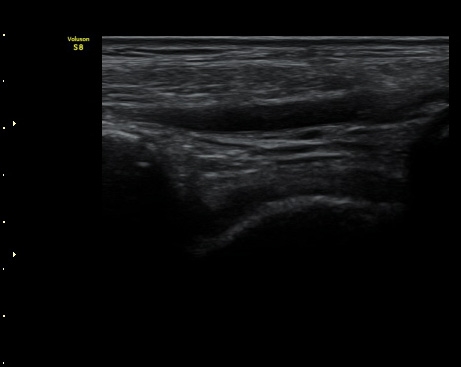

3ÁÖ ÈÄ ÃßÀû°Ë»ç¿¡¼­ ¹Ú¸®µÈ°ñÆíÀÌ °üÂûµÇ°í ÀδëÀÇ Àú¿¡ÄÚ ºÎÁ¾Àº ¾à°£

Áõ°¡µÈ ¼Ò°ßÀ» º¸ÀÓ(±×¸² 3, 4).